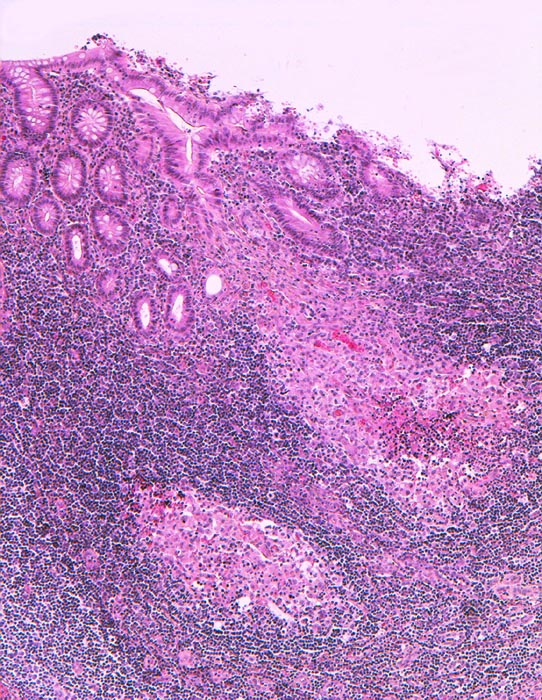

Retikulozytär abszedierende Entzündung bei Yersiniose

Ansammlung von Histiozyten mit zentraler granulozytärer Abszedierung im Stroma der Mucosa. Das Epithel ist intakt.

Eitrige Peritonitis.

Der histologische Befund ist charakteristisch aber nicht beweisend für eine Yersiniose. Dazu braucht es den zusätzlichen Nachweis von Yersinia pseudotuberculosis im Stuhl oder serologisch. Typisch ist die mesenteriale Lymphadenitis.